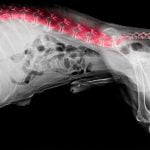

Mon chien a mal au dos